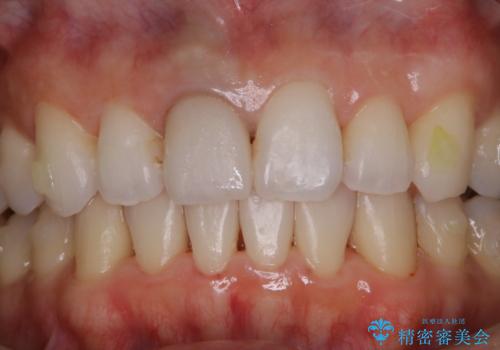

またPMTCを行うことで、ご自身本来の歯の色になり自然な明るさになります。

口元が自然な明るさになることで、より清潔感のある印象になるため結婚式・行事やイベント前などにもPMTCを行うはおすすめです。